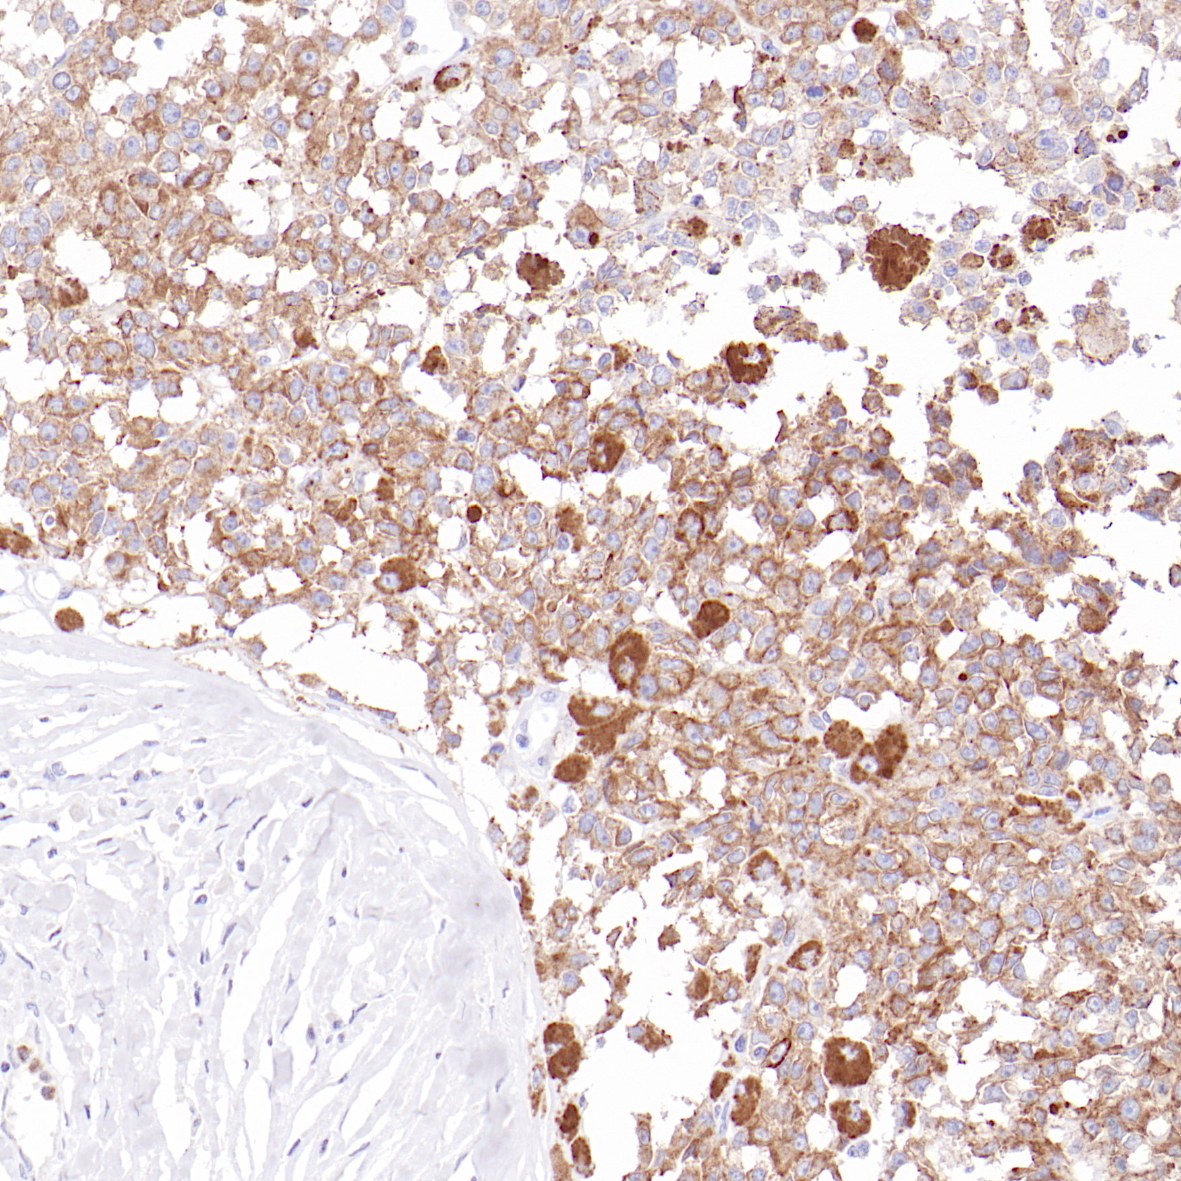

CDX2是一种同源框基因,是编码肠器官发生所必需的核同源结构域转录因子。CDX2对肠,胰腺和胆道上皮分化至关重要。CDX2与肿瘤抑制基因APC和E-cadherin以及bcl-2相互作用。在肠道(从十二指肠到直肠),CDX2核蛋白在所有类型的上皮细胞中被强烈且均匀地表现出来。在胰腺和胆道中,CDX2蛋白在散落的导管细胞中被呈现出来。在肿瘤组织中,CDX2在绝大多数结直肠腺癌和阑尾腺癌中是阳性表达的。CDX2是“肠”腺癌的相对敏感和特异性标记物。在未知原发部位(腺癌)的分类中,CDX2是一个重要的标记物,但应始终包括在检测组合中。同样为了鉴定神经内分泌肿瘤的起源,CDX2应在组合检测中。

CDX-2抗体试剂(免疫组织化学)

结肠